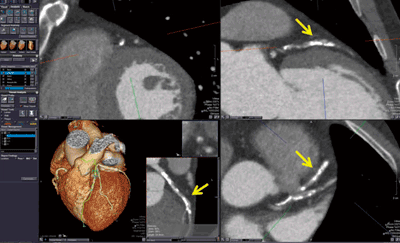

■心臓を機能的に評価する

“CT Cardiac Functional Analysis” アプリケーションでは,左心室・右心室の容積計測などの心機能解析が可能で,虚血性心疾患および中隔欠損症などの先天性疾患の診断に有効である。心位相間隔10%などで再構成された全心位相範囲の4D画像を読み込み,各心拍位相画像にて左心室,右心室,左心房を自動セグメンテーションし,1心拍における駆出率,心拍出量等のパラメータを算出することができる。左心室,右心室の拍出量の差などから,中隔欠損などによる異常流量を推測することができる。VR画像は位相方向への動画表示にて観察することも可能であり,容積変化の異常を視覚的に観察することも可能である(図3)。左心室に関しては,壁運動,壁厚変化率,局所駆出率等の心機能パラメータをPolar Map形式で表示でき,心機能面からの虚血性心疾患の診断にも活用できる。

心機能解析に必要な画像を得るためには,全心位相範囲での撮影が必要になるため,X線被ばく量が多くなってしまう。先天性疾患の診断は小児も対象になることから,被ばく量に対する配慮は重要であり,1回転で心臓全体をカバーでき,1,2心拍程度で全心拍位相範囲の撮影を完了できるAquilion ONEとの組み合わせが有効である。

図3 CT Cardiac Functional Analysis解析例

(画像ご提供:藤田保健衛生大学病院様)